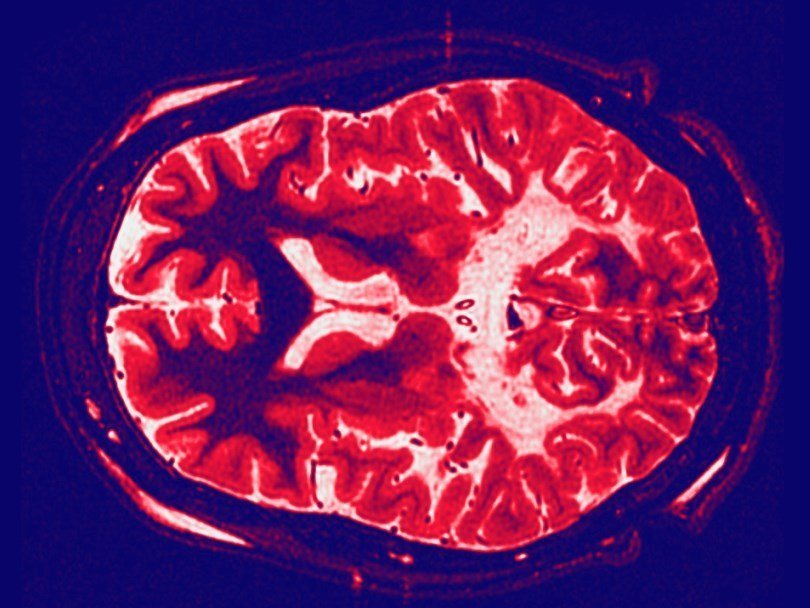

Мозг больного адренолейкодистрофией. Белые области - те, где утрачен миелин Frank Gaillard/Creative Commons На ежегодной конференции Американского общества генной и клеточной терапии было сделано сообщение об успешном применении генной терапии для лечения редкого генетического заболевания мозга – адренолейкодистрофии. Шестнадцать из семнадцати мальчиков, участвовавших в эксперименте, остаются относительно здоровыми уже в течение двух лет после того, как специально сконструированный вирус принес в их клетки ген, нужный для производства белка, необходимого их организму.

При исследовании мозга этих пациентов, проведенном два года спустя, выяснилось, что у большинства из них нет никаких признаков воспаления или утраты миелина. У 16 пациентов не наблюдается и характерных симптомов болезни: потери зрения или затруднений при ходьбе.